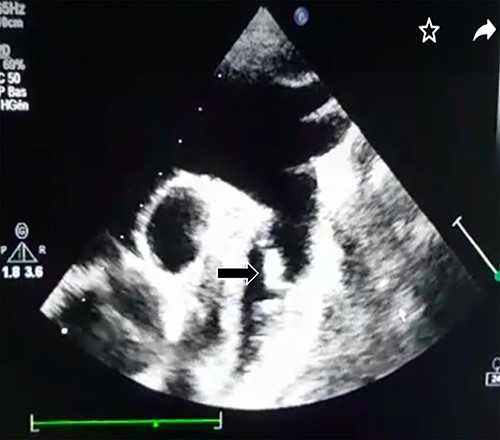

Transthoracic echocardiography revealed a large PDA (10 mm) with left-to-right shunt and a fixed structure on the wall of the pulmonary artery, with erratic movement indicative of a vegetation (Fig. 1), and mobile vegetation attached to the wall of the descending aorta in the supra-sternal view (Fig. 2) and a left ventricle with conserved systolic function and 55-mm end-diastolic diameter.

Supra-sternal view: vegetation attached to the wall of the descending aorta.